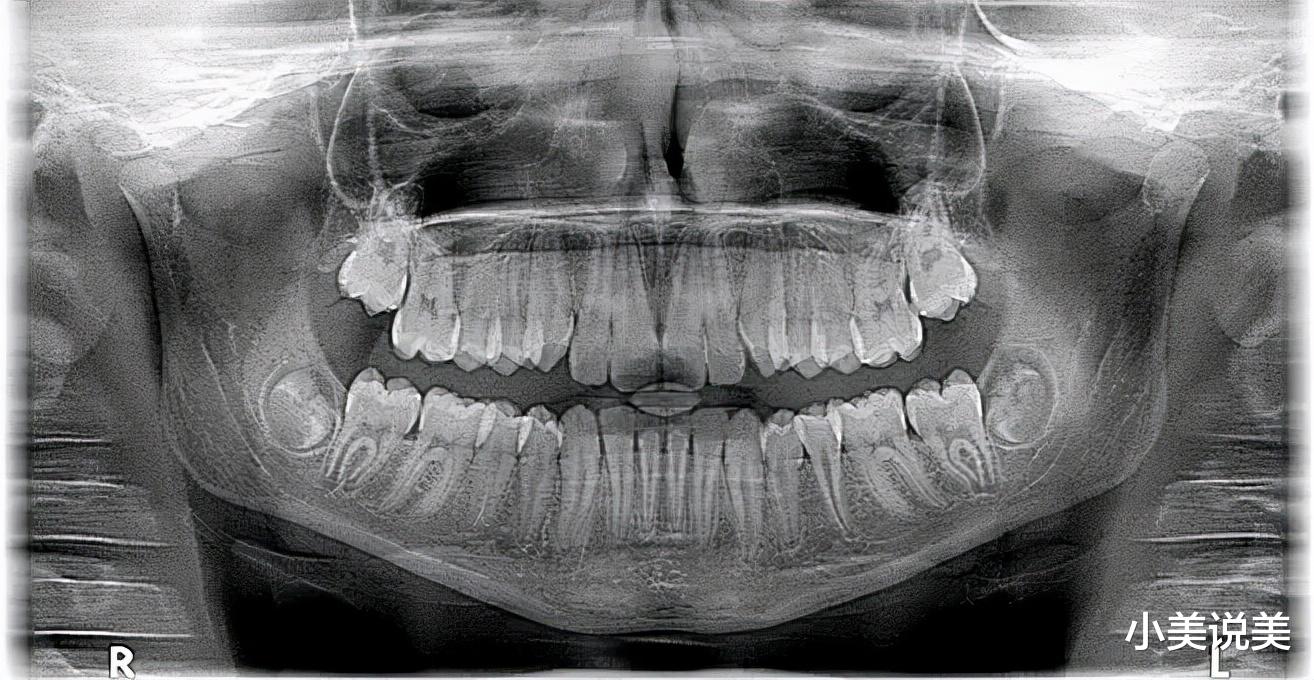

智齿在X线片上很清晰▼

由于萌出位置不足 , 智齿可能部分或全部被龈瓣覆盖 , 再加上位于口腔的最内侧 , 刷牙的时候十分难清理到 , 导致细菌滋生引发智齿冠周炎 , 进而使开口活动、咀嚼、吞咽疼痛加重 。